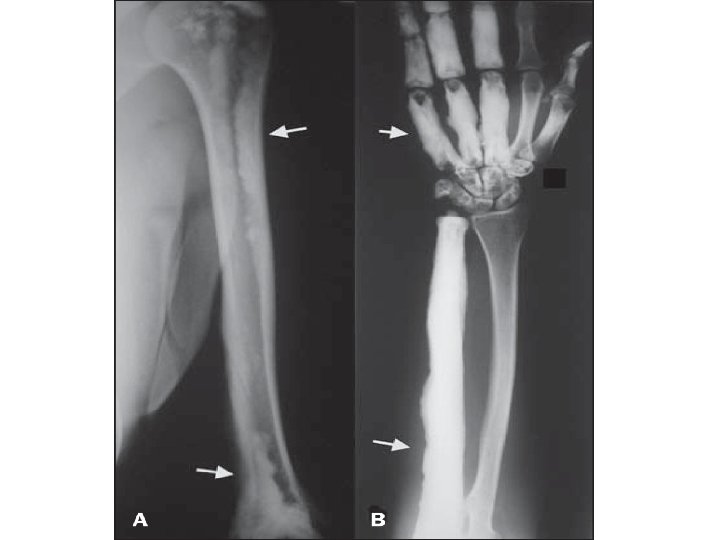

MELORHEOSTOSIS One of a rare group of sclerosing bone disorders Produces thickening of the endosteum and periosteum and common in lower extremities. Monostotic, monomelic or polyostotic Candle-wax appearance (classic)